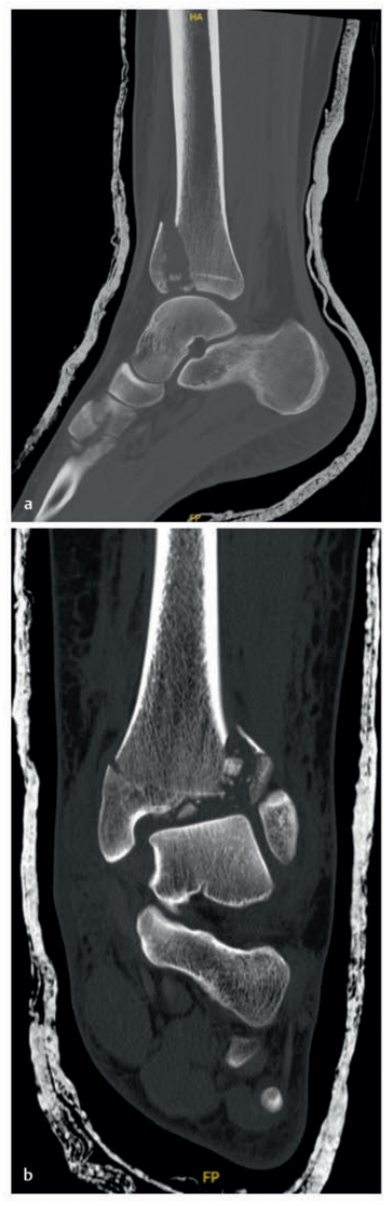

病例1在受伤后送往医院急诊,首先进行了跨踝关节外固定架。尽管患者初始存在Ⅱ度闭合性软组织损伤,但由于及时进行了复位并植入外固定架,未需实施筋膜间室切开术。在术前CT图像中,可清晰观察到3个主要骨折块及1个中央粉碎区。通过及时植入外固定架,可恢复关节位置,并有效避免软组织损伤进一步加重。

待软组织状况改善(出现 “皮肤皱纹征”)后,开始对患者进行手术治疗,首先处理腓骨(遵循 “先处理腓骨” 原则)。术中检查发现韧带联合存在不稳定情况。

术中三维CT 扫描确认骨折达到解剖复位,内植物位置良好。术后影像学检查证实骨折解剖复位,内植物位置正常。患者术后恢复过程顺利,关节功能恢复良好。